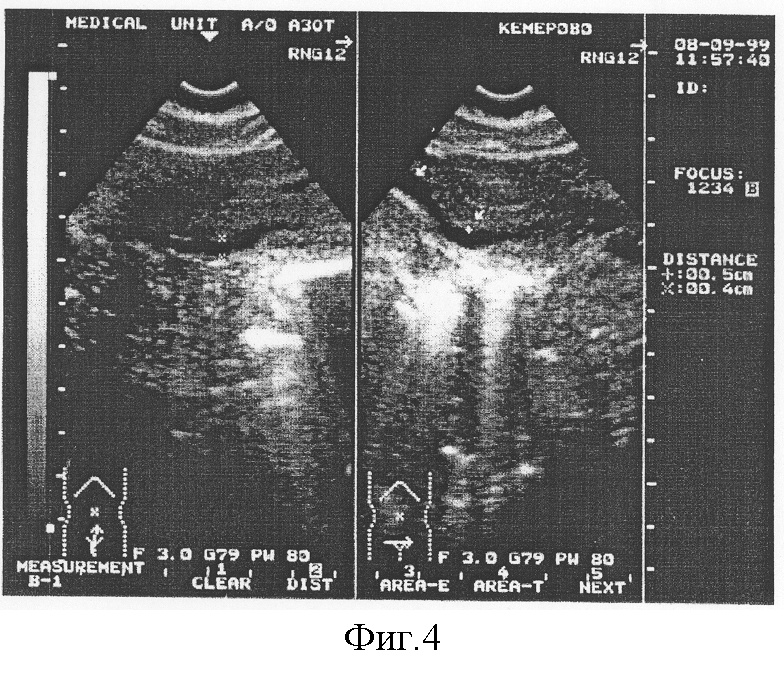

Пример 3. Больная З., 17 лет. История болезни №12372.

Поступила в гинекологическое отделение ГКБ №3 им.М.А.Подгорбунского 08.09.1999. с диагнозом: Эндометриоз, вторичное бесплодие трубно-перитонеального генеза.

При ультразвуковом исследовании диаметр маточных вен составил 0,6 см справа и 0,5 см слева; диаметр внутренних подвздошных вен составил 1,6 и 1,9 см соответственно, диаметр яичниковых вен 0,3 и 0,3 см соответственно; диаметр аркуатных вен 0,2 см. Диагноз: Варикозное расширение внутренних подвздошных вен?

Для подтверждения диагноза проведено исследование согласно предлагаемому способу.

Получены следующие результаты: диаметр маточных вен составил 0,6 см справа и 0,6 см слева; диаметр внутренних подвздошных вен составил 1,9 и 2,1 см соответственно, диаметр яичниковых вен 0,3 и 0,3 см соответственно; диаметр аркуатных вен 0,3 см (фигура 4).

Проведенное исследование позволило обозначить полученные данные как варикозное расширение внутренних подвздошных вен, что позволило установить правильный диагноз у данного пациента.